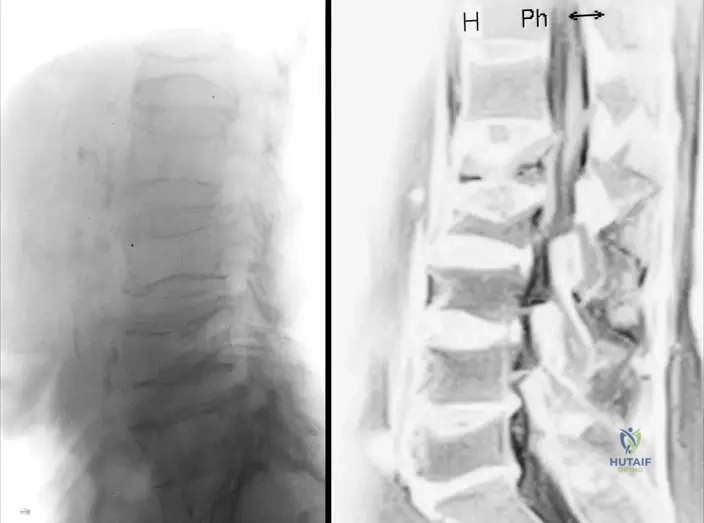

A 9-year-old girl with mesomelic dwarfism (Langer type) undergoes a lower extremity radiographic series due to progressive bowing of her lower legs and difficulty with ambulation.

View Answer & Explanation

Correct Answer: C

Rationale: The case text lists "tibio-fibular... synostosis" as a characteristic feature of mesomelic dwarfism (Nievergelt and Langer Type), affecting the lower limbs.

Main Distractor: D) Talo-calcaneal synostosis - While intertarsal synostosis is mentioned, tibio-fibular synostosis is a more prominent and specific long bone synostosis described in the lower leg, directly contributing to lower leg deformities.